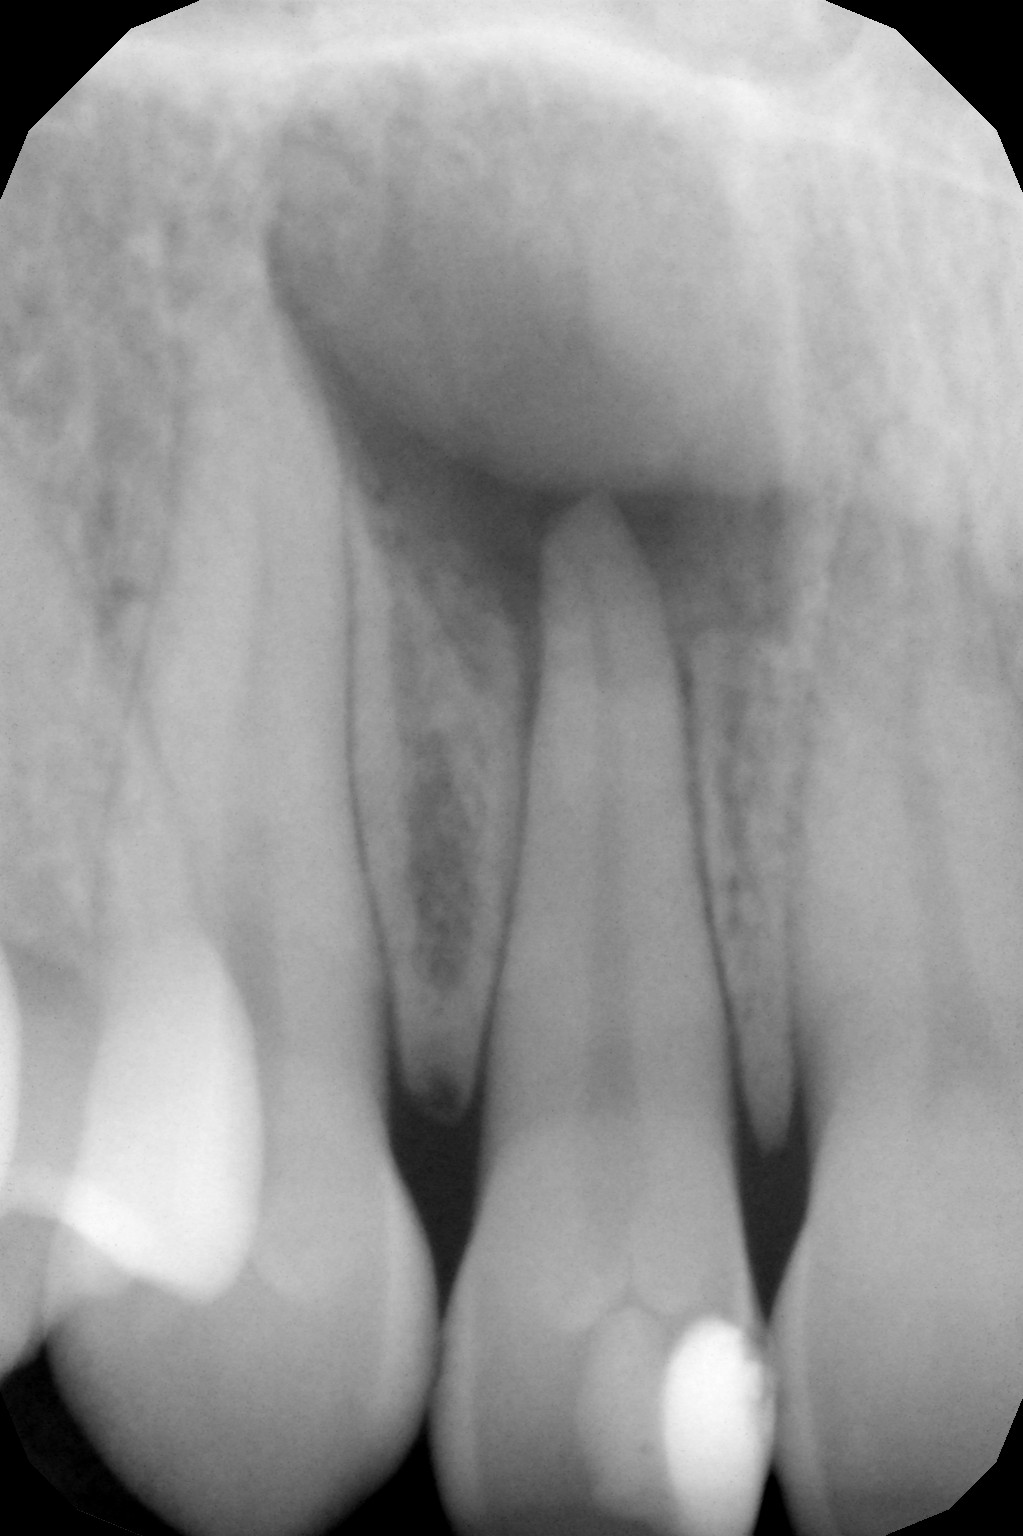

ODONTOIATRIA CONSERVATIVA

- Diagnosi precoce della carie mediante transilluminazione laser

- Valutazione del rischio di carie basso, moderato ed alto

- Tecniche restaurative adesive dirette e indirette